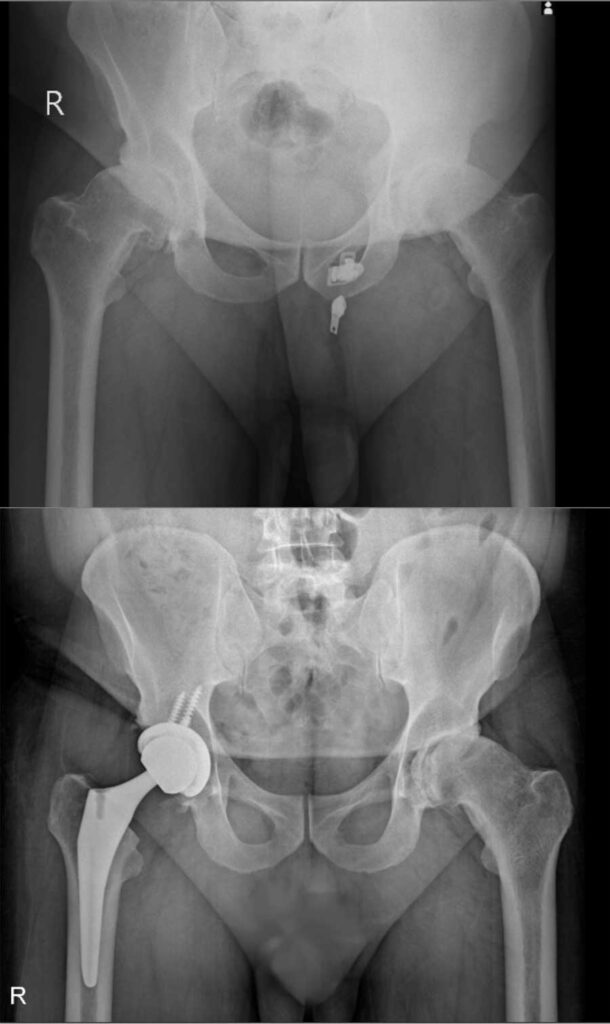

عکس تعویض مفصل لگن

برای آشنایی با تصاویر واقعی رادیوگرافی لگن قبل و بعد از جراحی، عکس تعویض مفصل لگن چند بیمار در زیر وجود دارد. با کلیک بر روی هر کدام از آنها تصویر بزرگتر و کامل را خواهید دید.